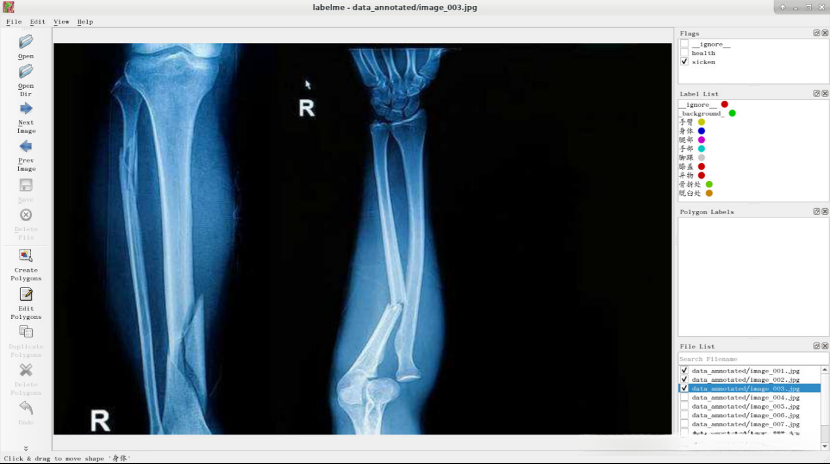

点击“Next Image”,判断健康状况并选择相应的flag。

通过X光影像检查, 对患者的健康状况进行初步评估, 如有必要, 请在报告中标注病变区域